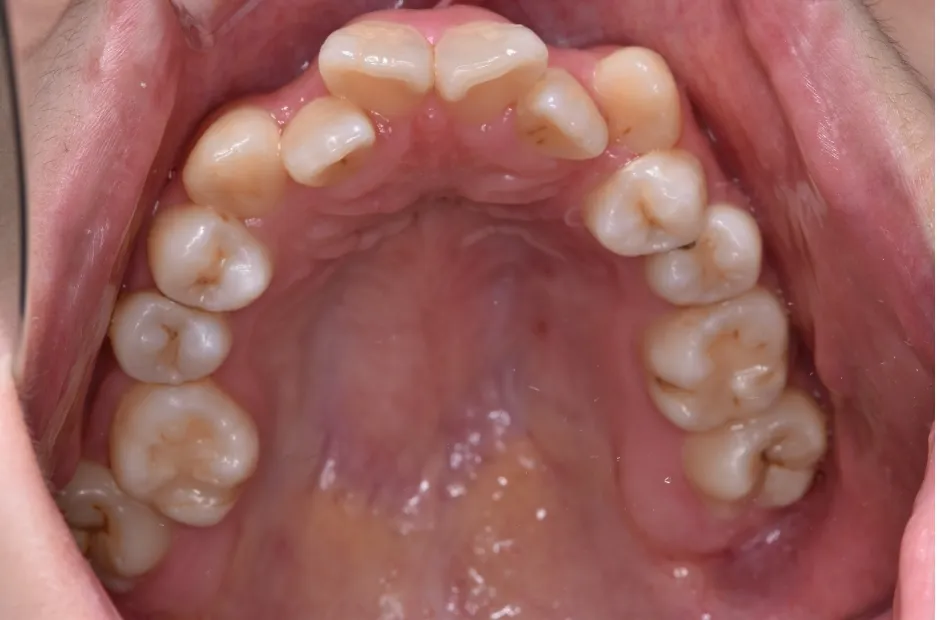

治療症例

ブラケット矯正

前歯部反対咬合

| 診断名・主訴 | 前歯部反対咬合 |

|---|---|

| 年齢・性別 | 14歳・男性 |

| 治療期間・回数 | 1年2か月 |

| 治療に用いた主な装置 | ブラケット矯正 |

| 抜歯部位 | なし |

| 治療費 | 60万円(税抜) |

| リスク・副作用 | 装置による違和感・疼痛・歯肉退縮・歯根吸収・虫歯のリスクなど |

治療前

治療後